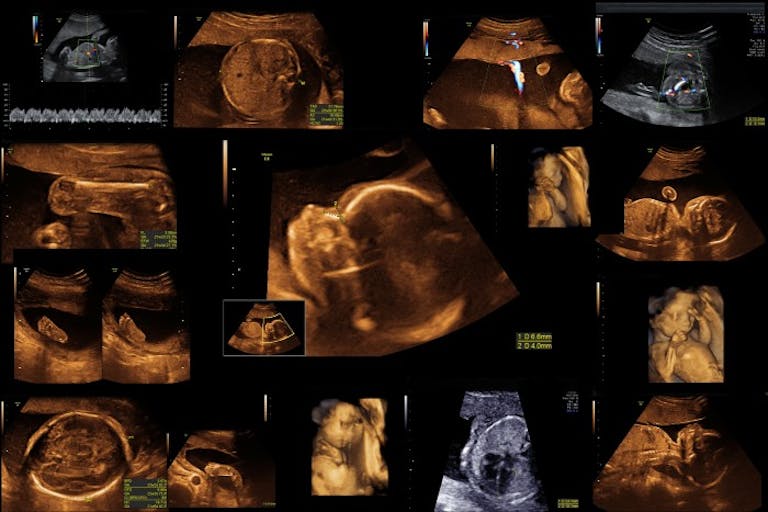

The argument lies in the fact that fetal abnormalities and disabilities are often diagnosed later in pregnancy. OB/GYN Daniel Grossman says, “The test to detect genetic and chromosomal abnormalities is usually performed at about 15 or 16 weeks of pregnancy, but it isn’t a catchall.”

He adds: “physical malformations caused by different factors aren’t likely to be detected until 18 weeks or later.”